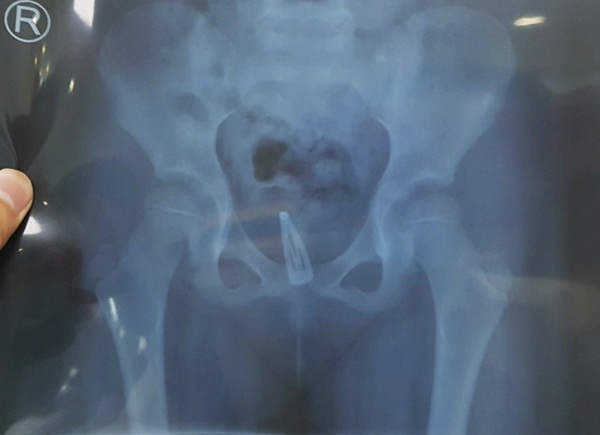

Tại đây bé được chụp X-quang bụng, thử nước tiểu, siêu âm bụng... Bé được chẩn đoán nhiễm trùng tiểu, có dị vật âm đạo, vùng kín viêm đỏ nhiều, niệu đạo có dịch mủ, âm đạo viêm đỏ có ít dịch vàng hôi.

Các bác sĩ khoa Ngoại Niệu và đơn vị Phẫu thuật trong ngày tiến hành nội soi gắp dị vật là cái kẹp tóc bằng kim loại đã rỉ sét do bị quá lâu nên oxy hóa trong âm đạo.